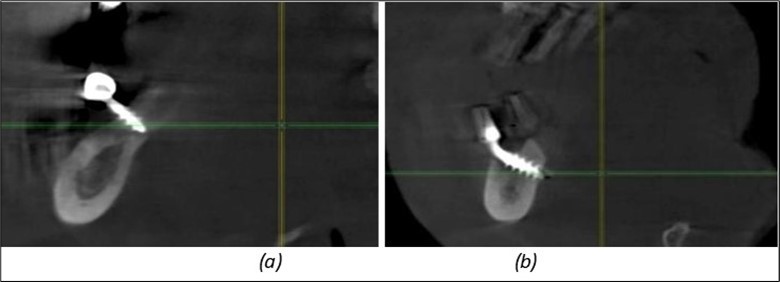

Figure 14.Rx panoramic final situation control: (a) Panoramic X-ray with the addition of a distal BCS implant in quadrant 3 at 11.2022; (b) Control X-ray, 10.2023.

Results

The results of rehabilitation treatment with corticobasal and compressive implants with a polished surface after the failure of two stage implants were highlighted over a period of 3 years and 3 months as being very good (Figure 14, Figure 15), with the patient completing a satisfaction survey in this regard. Certainly, it is necessary to continuemonitoring these results in the long term.